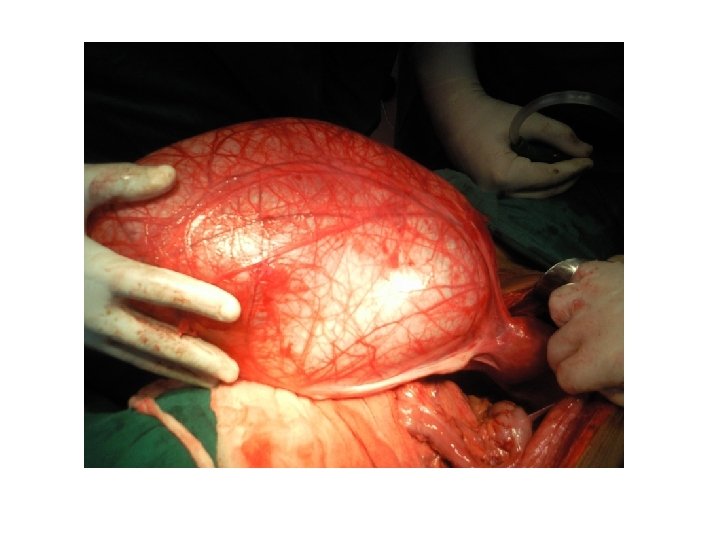

• DIAGNOZA DIFERENCIALE: - Me peritonitin akut nga ruptura te ndryshme si e apendiksit - Barra ekstrauterine - Pankreatit hemoragjik - Torsion ovarial

RUPTURE e shtatezanise ektopike:

• Cdo femer ne moshen e fertilitetit qe paraqitet ne urgjence me dhimbje te abdomenit te poshtem duhet te beje TESTIN E SHTATZANISE!!!!!!!